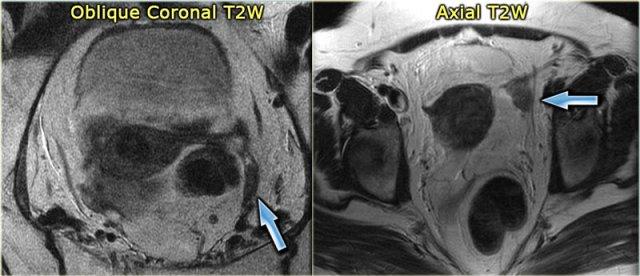

TRÁI: Phụ nữ sau mãn kinh. Buồng trứng là một cụm mô giảm tín hiệu T2W nằm gần đầu gần của dây chằng tròn. PHẢI: Buồng trứng trái giảm tín hiệu T2W, không có nang noãn. Buồng trứng hơi nổi bật nhưng vẫn có khả năng là bình thường

Trên ảnh MRI chuỗi xung T2W mặt phẳng coronal của một phụ nữ sau mãn kinh, buồng trứng chỉ là một cụm mô giảm tín hiệu nằm gần đầu gần của dây chằng tròn.

Ảnh MRI chuỗi xung T2W mặt phẳng axial cũng cho thấy buồng trứng trái giảm tín hiệu, không có nang noãn.

Mặc dù hơi nổi bật, đây có khả năng là hoàn toàn bình thường.

Chỉ khi tình cờ có hình ảnh trước đó cho thấy tổn thương đang phát triển, chẩn đoán phân biệt mới bắt đầu với các tổn thương đặc lành tính như u xơ buồng trứng hoặc u xơ-vỏ buồng trứng.